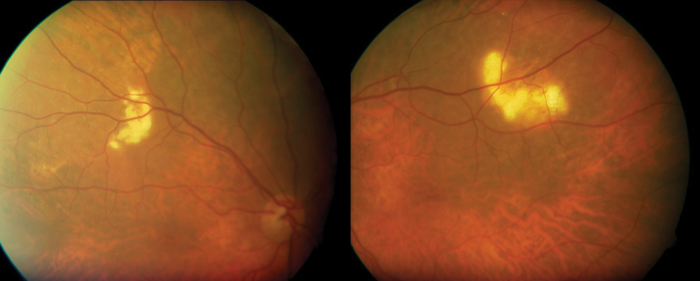

Figure 2.

An 83-year-old caucasian male was referred by his optometrist querying the cause of bilateral superotemporal fundal lesions. The patient was visually asymptomatic with an unremarkable past medical history. Clinically visual acuity was Right: 0.36 logMAR improving to 0.26 logMAR with pinhole and Left: 0.6 logMAR improving to 0.04 logMAR with pinhole. The anterior segment assessment showed moderate cortical lens opacity bilaterally and dilated fundoscopy revealed evidence of slight raised yellowish lesions (Figure 1) on the superior aspect of the superotemporal arcade bilaterally. B-scan ultrasound examination revealed highly reflective lesions and confirmed the clinical diagnosis of bilateral sclerochoroidal calcification (Figure 2).